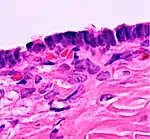

Histopathology

In case an ovarian cyst is surgically removed, a more definite diagnosis can be made by histopathology:

TypeSubtypeTypical microscopy findingsImage

Functional cystFollicular cyst

Corpus luteum cyst

CystadenomaSerous cystadenoma Cyst lining consisting of a simple epithelium, whose cells may be either:[21]

• columnar and tall and contain cilia, resembling normal tubal epithelium

• cuboidal and have no cilia, resembling ovarian surface epithelium

Mucinous cystadenoma Lined by a mucinous epithelium

Dermoid cyst Well-differentiated components from at least two germ layers (ectoderm, mesoderm and/or endoderm).[22]

Endometriosis At least two of the following three criteria:[23]

Borderline tumor Atypical epithelial proliferation without stromal invasion.[24]

Ovarian cancer Many different types, but generally severe dysplasia/atypia and invasion.

Simple squamous cyst Simple squamous epithelium and not conforming to diagnoses above (a diagnosis of exclusion)